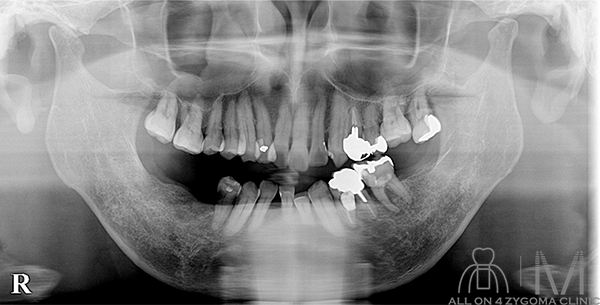

術前パノラマ画像所見